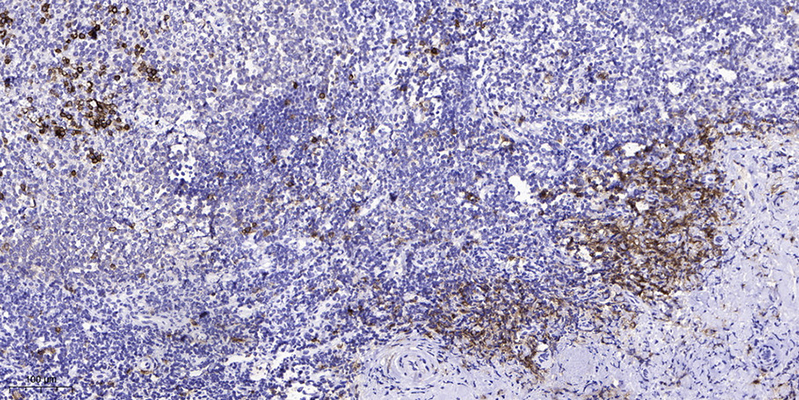

IHC-P,IF-P,IF-F,ICC/IF,ELISA

WB 1:500-2000, IHC-P 1:100-1:300, ELISA 1:5000, IF-P/IF-F/ICC/IF 1:50-200